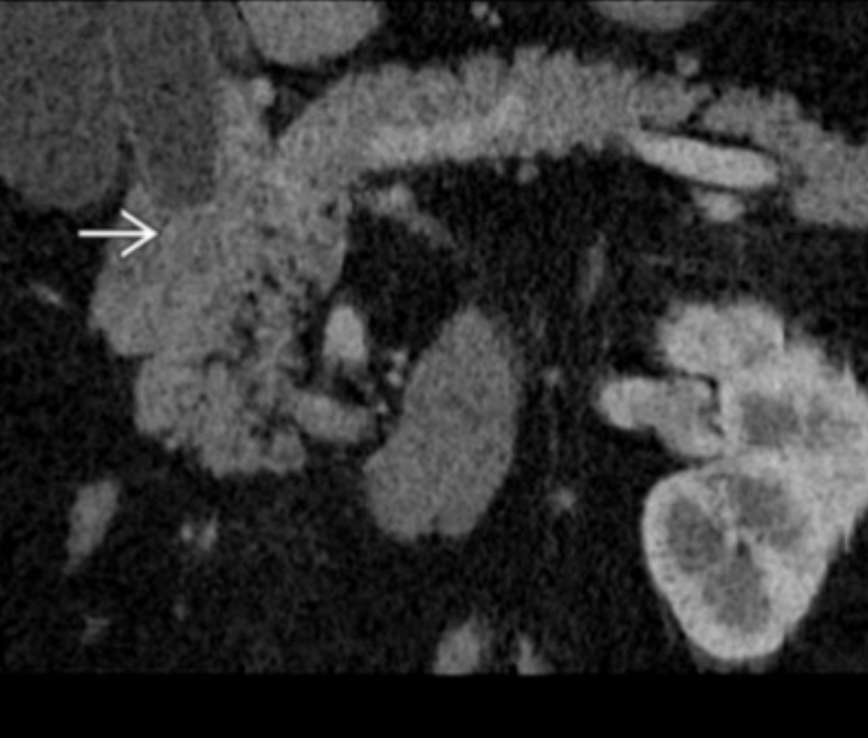

Bile duct infection/inflammation: recurrent pyogenic cholangitis (Oriental cholangiohepatitis)

Px: bug involved; what does this lead to?

Ex: where?

Ix: triad.

Sequela-1